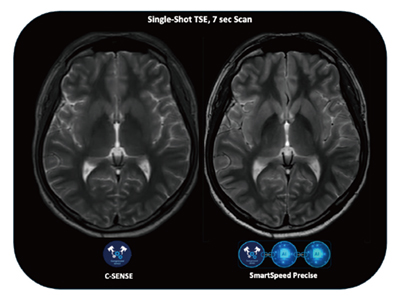

図2では,シングルショット7秒スキャンを比較している。3.5倍速によるブラーリングの軽減に加えて,SmartSpeed Preciseでは,再最適化されたサンプリングやPrecise Netの効果により鮮鋭度が高く保たれている。高速化と高画質化を兼ねたDLRのアドバンテージを生かすアプリケーションになりうると期待している。

図2 シングルショット全脳T2強調画像7秒スキャン

(プロトコールご提供:北海道大学病院・藤間憲幸先生)